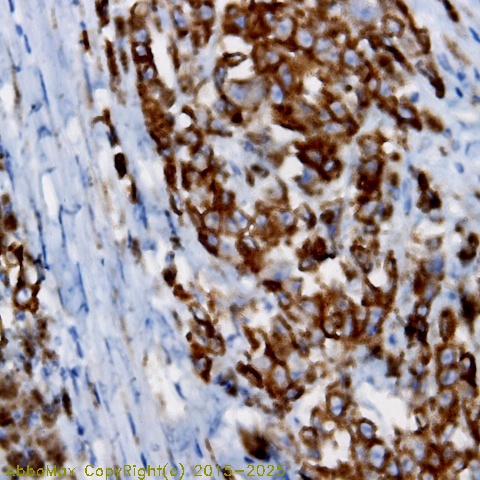

IHC

2-10 µg/ml

Applications: IHC(P), WB